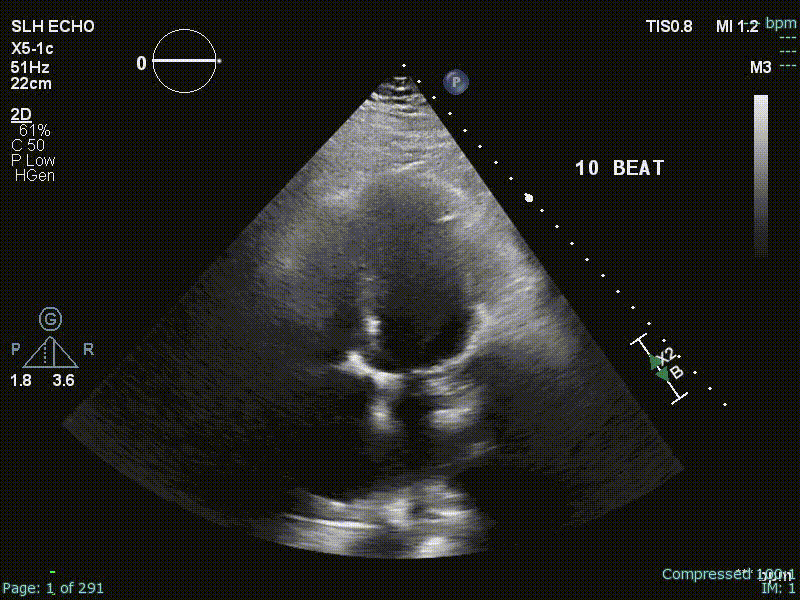

Echo

“Echo diagnosis of constriction is all about pattern recognition” - Sanjiv Shah

Ventricular Interdependence? Think constriction

Constrictive physiology should be considered when evidence of enhanced interdependence is observed by echocardiography.

- Diastolic septal bounce

- Dilated IVC

- Diastolic flow reversal during expiration

- Hepatic vein flow reversal increases with expiration

- “The hepatic vein doppler is very helpful in atrial fibrillation in patients with constrictive pericarditis to differentiate them from restrictive physiology. And so if you think about hepatic inflow, the hepatic vein should be draining into the IVC and then into the right atrium. And so if a patient has constrictive pericarditis, what happens with expiration? That septum’s blowing towards the right side, and that pressure is being transmitted from the RV to the RA to the IVC back up to the hepatic veins. So that you have ==diastolic flow reversal in hepatic veins predominantly during expiration== if the patient has constricted pericarditis. It’s all along the same track from the LV to the RV to the RA, IVC, and hepatic veins.

- Conversely, if a patient has restrictive physiology, what happens is the majority of the inflow to the right side, just like in normal healthy hearts, will happen during inspiration. However, the restrictive, stiff, non-compliant right ventricle, it’s not able to fully accept all that blood during inspiration. And so during inspiration, when you get that huge bolus going into the RV, it’s not going to be able to accept it. And so you get the pressure referred all the way backwards into the hepatic veins. And so ==with the restrictive physiology, you get diastolic flow reversal in the hepatic veins, predominantly in inspiration.==”